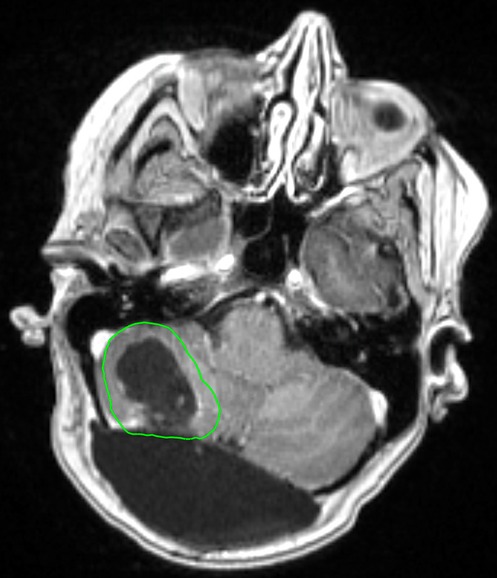

The development of LMD is a significant concern in patients with brain metastases, particularly following surgical resection. Mahajan et al. observed an approximately 25% LMD rate in the postoperative SRS arm (16). In a 2017 study by Foreman et al., a 35% LMD rate at 1 year following postoperative SRS was observed (47). Additionally, they observed trend towards an increased risk of developing LMD in patients with breast cancer histology (HR: 2.37; p = 0.07). A study by Atalar et al. that evaluated 175 brain metastasis resection cavities that were treated with postoperative SRS observed an 11% cumulative incidence of LMD at 1 year (46). They also noted a 24% LMD rate in breast cancer patients compared to 9% in patients with other histologies (p = 0.004). Furthermore, resection and postoperative SRS is associated with a particular subtype of LMD, known as nodular LMD (nLMD) (45, 80). A radiation treatment plan for a patient who underwent resection and postoperative SRS is presented in Figure 1.

FIGURE 1

www.frontiersin.org

Figure 1. Radiation treatment plan of a 65 year old female patient with a history of breast cancer. She underwent a surgical resection followed by postoperative SRS to the resection cavity (outlined in green) to a dose of 27 Gy in 3 fractions.